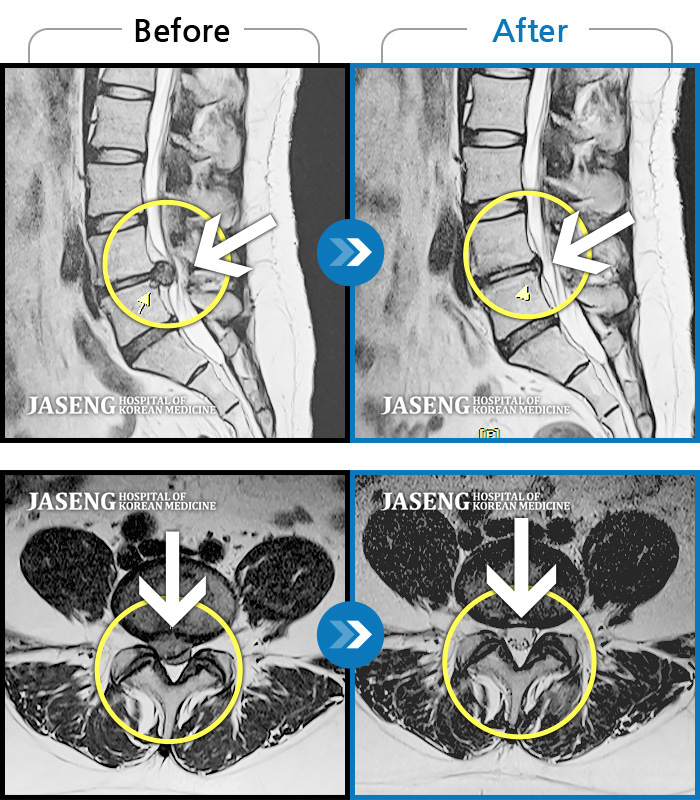

허리디스크

광주 · 김동은 원장

양측 허리부터 양측 골반까지 당기는 통증, 양측 하지 후면으로 이어지는 통증

촬영시기

2022.09.05 ~ 2024.05.06

2024.05.24